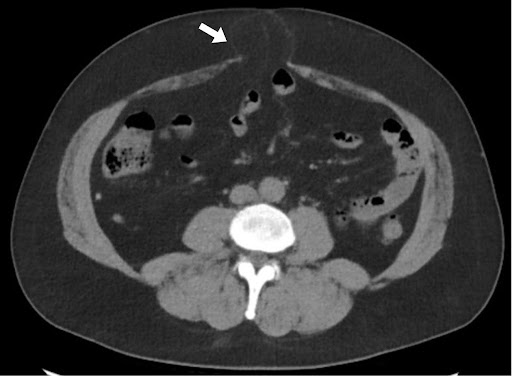

पेट और श्रोणि के गैर-विपरीत बढ़ाया सीटी ने अक्षीय इमेजिंग पर दो वसा युक्त मिडलाइन हर्निया दोषों का प्रदर्शन किया। यूरोपीय हर्निया सोसाइटी (ईएचएस) वर्गीकरण के अनुसार, ये एक एम 2 हर्निया के अनुरूप हैं जो चौड़ाई में 16 मिमी और क्रानियोकौडल लंबाई में 8 मिमी मापते हैं, और एक एम 3 हर्निया की चौड़ाई 37 मिमी और लंबाई में 30 मिमी है। धनु पुनर्निर्माण ने अतिरिक्त फेशियल दोषों के साथ-साथ पूर्व मिडलाइन चीरा के साथ क्षीण प्रावरणी के क्षेत्रों का खुलासा किया, जो सबक्लिनिकल हर्निया के अनुरूप था।

चित्रा 1 अक्षीय छवियों पर वसा युक्त एम 2 और एम 3 हर्निया को दिखाता है। धनु विचार पैथोलॉजी का अधिक व्यापक चित्रण प्रदान करते हैं, M1-M3 क्षेत्रों में फैले क्षीण प्रावरणी का प्रदर्शन करते हैं, अतिरिक्त इंटरपेरिटल हर्निया दोषों (धराशायी तीर) का विचारोत्तेजक फेशियल उतार-चढ़ाव, और M2 ज़ोन (तीर) से बेहतर एक छोटा हर्निया दोष जो अक्षीय इमेजिंग पर स्पष्ट नहीं था।

चित्रा 1. अक्षीय और धनु विचारों के साथ सीटी पेट और श्रोणि। सीटी इमेजिंग मिडलाइन वसा युक्त हर्निया दोषों का प्रदर्शन करती है।